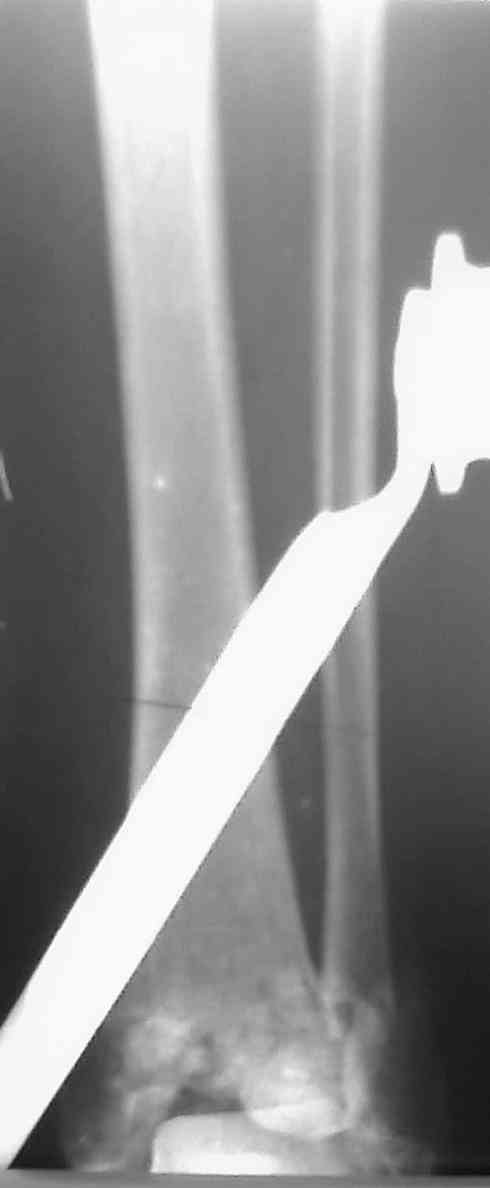

Уважаемый Коваленко А.Н. Последний месяц у меня было три операции на голеностопном суставе с похожим послеоперационным течением. Обошлось без нагноения.

1. Если на третий день после операции появился и усиливается отек - причина в ране, нагноение гематомы. После столь травматичной операции, следовало бы производить активную аспирацию в течение 2-3 дней или хотя бы дренировать раны. В настоящее время, я бы, терять уже нечего, прошел желобоватым зондом в зону перелома и выпустил гематому. Обычно - достаточно, если сделаете вовремя.

2. Второе. Следует обязательно усилить фиксацию: спицы через передний отдел стопы и пяточную кость, вторая спица через проксимальное кольцо и 1-2 стержня в проксимальный отломок б/б кости. Сроки фиксации до 8 недель. Аппаратом можно устранить, кажется, появившийся вальгус. В подобных ситуациях лучше ведут себя стержни, которыми можно сопоставить и сдавить лодыжки и задний край б/б кости. Привожу случай восстановления голеностопного сустава спустя 2,5 мес.(этап лечения) после травмы со стержнями.

3. Дистальную опору можно было бы взять в виде ¾ кольца или двух разноуровневых полуколец, соединенных небольшими стяжными стержнями. ¾ кольца - не давят на стопу, а разноуровневые полукольца «обходят» сустав. Одно снизу, другое сверху.

4. Антибиотики не менее 5 дней, и это уже лечение, затем если остаются признаки раневой инфекции (температура, СОЭ, L, отек) смена антибиотиков.

5. О клексане. 28 лет, дистальный отдел конечности - максимум 3 дня с переходом на непрямые антикоагулянты под контролем длительности кровотечения и протромбинового индекса.

6. На голень - УФО, субэритемные дозы. Обязательно. Помогает.

Поспешите. Все обойдется. Виктор.

Р-снимки.doc